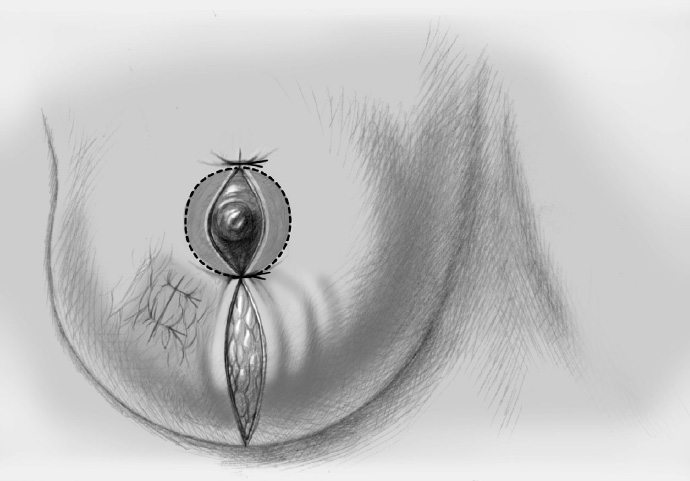

The periareolar skin is de-epithelialized. Here, too, there are various options. A strip of the most superficial skin layer can be excised with dissecting scissors applied flat or with a scalpel. It is important not to leave behind any surface containing squamous epithelium, but on the other hand the dermis and the important vascular layer beneath it must not be injured. The purpose of periareolar de-epithelialization is to recenter the nipple–areola complex and also to tailor excess skin to the new breast shape following extensive tumor resection.

The former tumor region is marked with clips.

The former tumor bed is marked with clips for optimized postoperative radiotherapy.

A Redon drain is placed prior to approximation of the breast lobes.

The mobilized breast lobes are rotated into the defect and approximated by interrupted sutures. Complete covering of the defect is desirable.

The skin is closed in two layers with recentering of the nipple–areola complex using interrupted sutures (Vicryl 3–0) according to the preoperative de-epithelialization pattern, which can be corrected at this time.